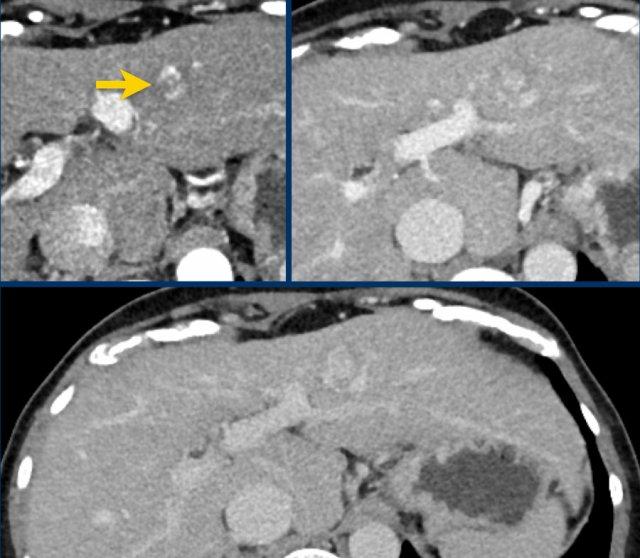

Các hình ảnh cho thấy một tổn thương ngấm thuốc động mạch dạng viền nhẹ ở phân thùy V có thải thuốc.

Có thể thấy một vùng giảm ngấm thuốc dạng tuyến tính kéo dài từ khối u, gợi ý khối u trong tĩnh mạch (mũi tên vàng).

Vì chúng ta không hoàn toàn chắc chắn đây là huyết khối do khối u, nên không thể phân loại trường hợp này là LR-TIV.

Một CT theo dõi được thực hiện, cho thấy tiến triển nặng của khối u cũng như xâm lấn mạch máu vào nhánh tĩnh mạch cửa phải trước (mũi tên trắng).

Lúc này chúng ta có thể xác định chắc chắn sự xâm lấn khối u vào tĩnh mạch cửa.